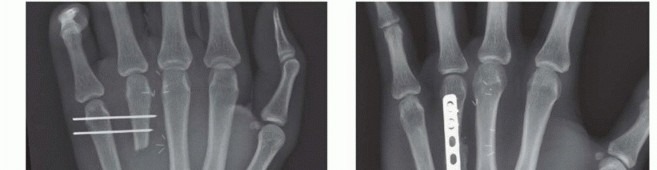

With high-quality imaging in hand, the surgeon must engage in precise surgical templating. This involves selecting the optimal fixation modality—be it Kirschner wires, lag screws, dorsal plates, or intramedullary headless screws—based on the fracture's personality. For a long, oblique diaphyseal fracture where the fracture length is at least twice the diameter of the bone, interfragmentary lag screw fixation alone may provide sufficient stability. Conversely, a comminuted, unstable midshaft fracture with bone loss will necessitate a rigid dorsal locking plate utilized in a bridging construct.

Implant sizing must be anticipated. Metacarpal plates are typically low-profile (1.2mm to 1.5mm thickness) to minimize extensor tendon irritation, utilizing 2.0mm or 2.4mm screws. The surgeon must template the plate length to ensure at least three cortices of fixation (ideally four to six) proximal and distal to the fracture zone. If intramedullary fixation is chosen, the canal diameter must be measured to select an appropriately sized headless compression screw (typically 3.0mm to 4.5mm) that will achieve adequate cortical purchase without causing iatrogenic bursting of the narrow diaphysis.

When a dorsal plate is required, it must be meticulously contoured to match the natural dorsal convexity of the metacarpal to prevent secondary displacement during screw insertion. For transverse fractures, the plate is applied in compression mode using eccentrically placed screws. For comminuted fractures, the plate functions as a bridge, bypassing the zone of comminution to maintain length and alignment without disturbing the fracture hematoma. Locking screws are utilized in osteoporotic bone or very short distal segments to prevent hardware pullout.

Clinical & Radiographic Imaging Archive